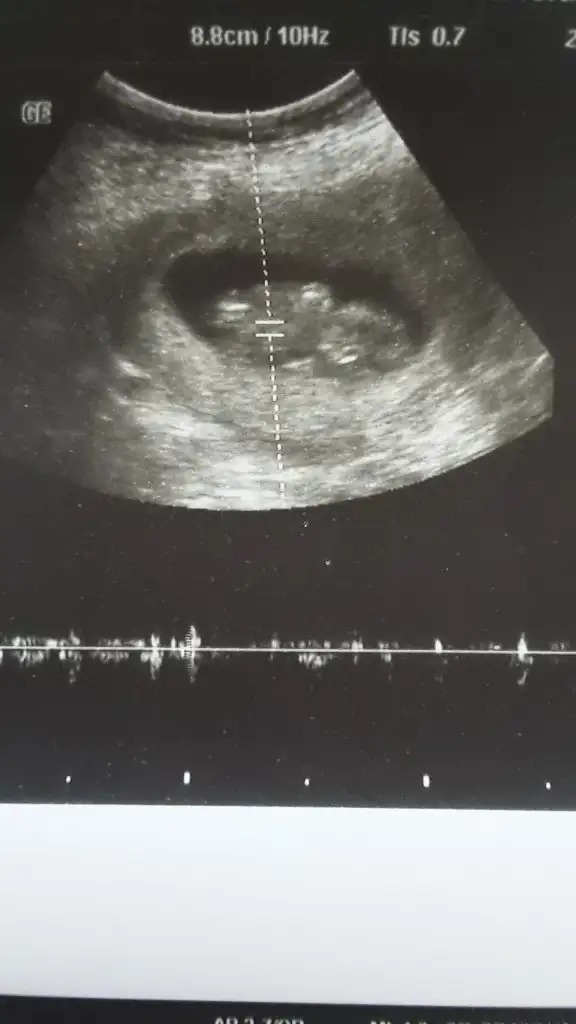

Her iki doktor farkli soyledi cinsiyetini 10ngun sonra kesin soyleriz dedi son fotograflar yeni bacak arasi net dikattli bakinca belki fikrin netlesir belki canimSanki erkek gibi 12 yada 13 hafta usgde paylaşın![]()

Burada kız gibi zaten 12 13 hafta usg istemiştim burada kaç hafta usgHer iki doktor farkli soyledi cinsiyetini 10ngun sonra kesin soyleriz dedi son fotograflar yeni bacak arasi net dikattli bakinca belki fikrin netlesir belki canim![]()

Usg net değil kaç hafta usg 12 13 de paylaşırsınız emin değilim sanki kızKızlar bizede tahminde buluna bilir misiniz vajinal ultrason![]()

11 12 13 hafta usg olmalı burada 14 haftada nub oluşmuş oluyor sanki emin değilim erkek gibi gibi istediğim usg leride paylaşın14 haftalık tahmin edermisiniz

Ancak 2 hafta sonra gidebilirim sokaga cikma yasagi olmazsaEvet burada daha önceki usg de nubu erkek gibi bacak arası usg göremedim buradaama 12 13 hafta usg istedim çünki net değildi halada 12 13 hafta usg bekliyorum

8+5günlük hafta var olursa ona bakın11 12 13 hafta usg olmalı burada 14 haftada nub oluşmuş oluyor sanki emin değilim erkek gibi gibi istediğim usg leride paylaşın![]()

Net değil 12 13 haftada paylaşın sanki eminde değilim erkek gibi gibi